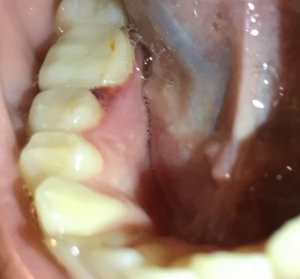

Доброго времени суток. Скажите пожалуйста: если болели зубы при накусывании в течение 2-х дней, болели не сильно, а потом прошли, то что это может быть? Спасибо.

Добрый день. В этом случае возможно на верхушках имеется воспаление. И оно, как правило, проявляется при снижении иммунитета. Я вам рекомендую обратится на очный прием к стоматологу-терапевту для составления плана лечения оперяясь на рентген снимки и на состояние зубов в полости рта. Запишитесь к нам на прием и мы обязательно вам поможем.